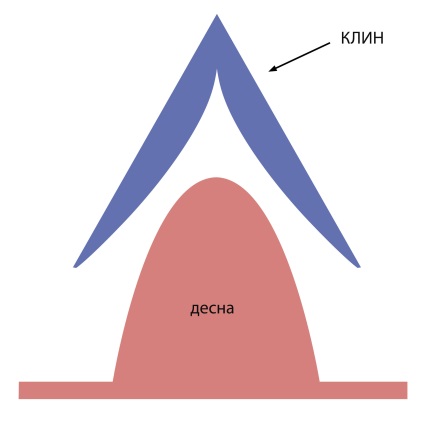

Astăzi, în piața dentare pot folosi diverse sisteme de matrice. Acestea pot fi împărțite în plat și contur circular și secționată. Pentru noi matrice concept de contur crucială. Conturat înseamnă că matricea este necesară pentru crearea unei suprafețe sferice a ecuatorului dintelui. Anatomia corectă a suprafeței proximale este o condiție esențială pentru buna funcționare a dintelui care formează papila și umplerea spațiului interdentar. În absența punctului de contact alimente fibroase dens se va lipi întotdeauna, ceea ce va duce în mod inevitabil la dezvoltarea inflamației în țesuturile parodontale.

Anatomia corectă a suprafeței proximale este o condiție importantă pentru buna funcționare a dinților, formarea papila gingivală și umplerea acestora interdentară

Pentru presarea matricei dintelui folosit nonpozitiv mare pană albă. Penei este format din două plăci dispuse la un unghi unul cu altul. După introducerea într-un decalaj de pană interdentară extinde peste papila fără al deteriora (Fig. 5).

pene convenționale când sunt administrate la strivire și vatămă papila gingivală, ceea ce duce la apariția sângelui după extragerea penei și lung proces de recuperare a tesutului guma.